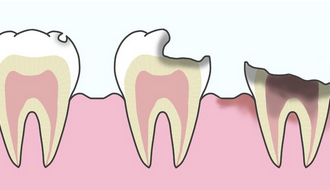

「虫歯を放置する危険性|学校医が伝える歯と健康の関係」

2025.11.28

詳細を見る虫歯を放置するとどうなるの? 学校で校医をしていると、「虫歯って放っておいても大丈夫?」「部活・受験が忙しくて・・・」という質問をよく受けます。 結論から言うと、虫歯は…